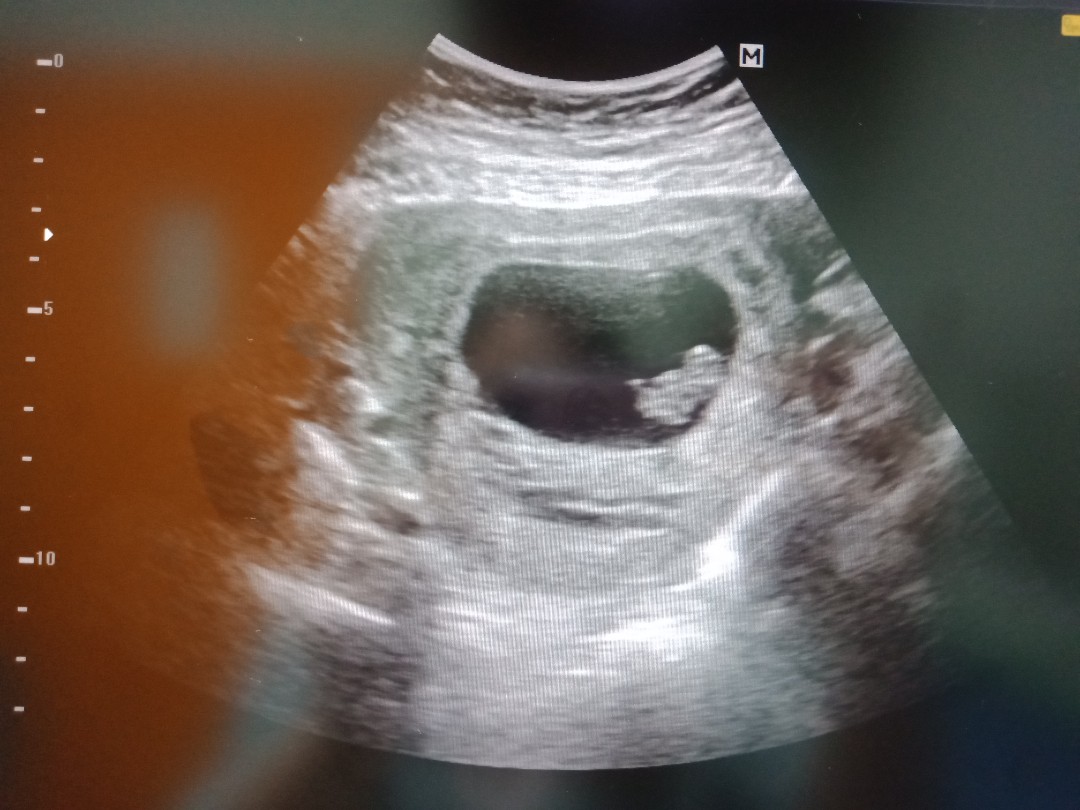

แม่ๆเห็นตัวเห็นหัวใจน้อง ตอนกี่สัปดาห์ค่ะ

ตอนนี้ 6 w เห็นแต่ถุง

8 วีคค่ะ